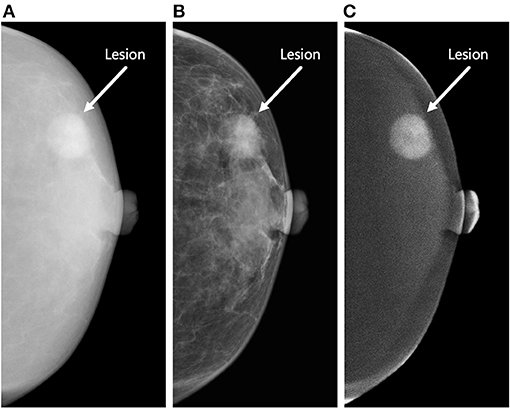

Tina Knowles Reveals Cancer Battle in New Memoir

## Tina Knowles Reveals Breast Cancer Battle in New Memoir, "Matriarch" Tina Knowles, mother of Bey...